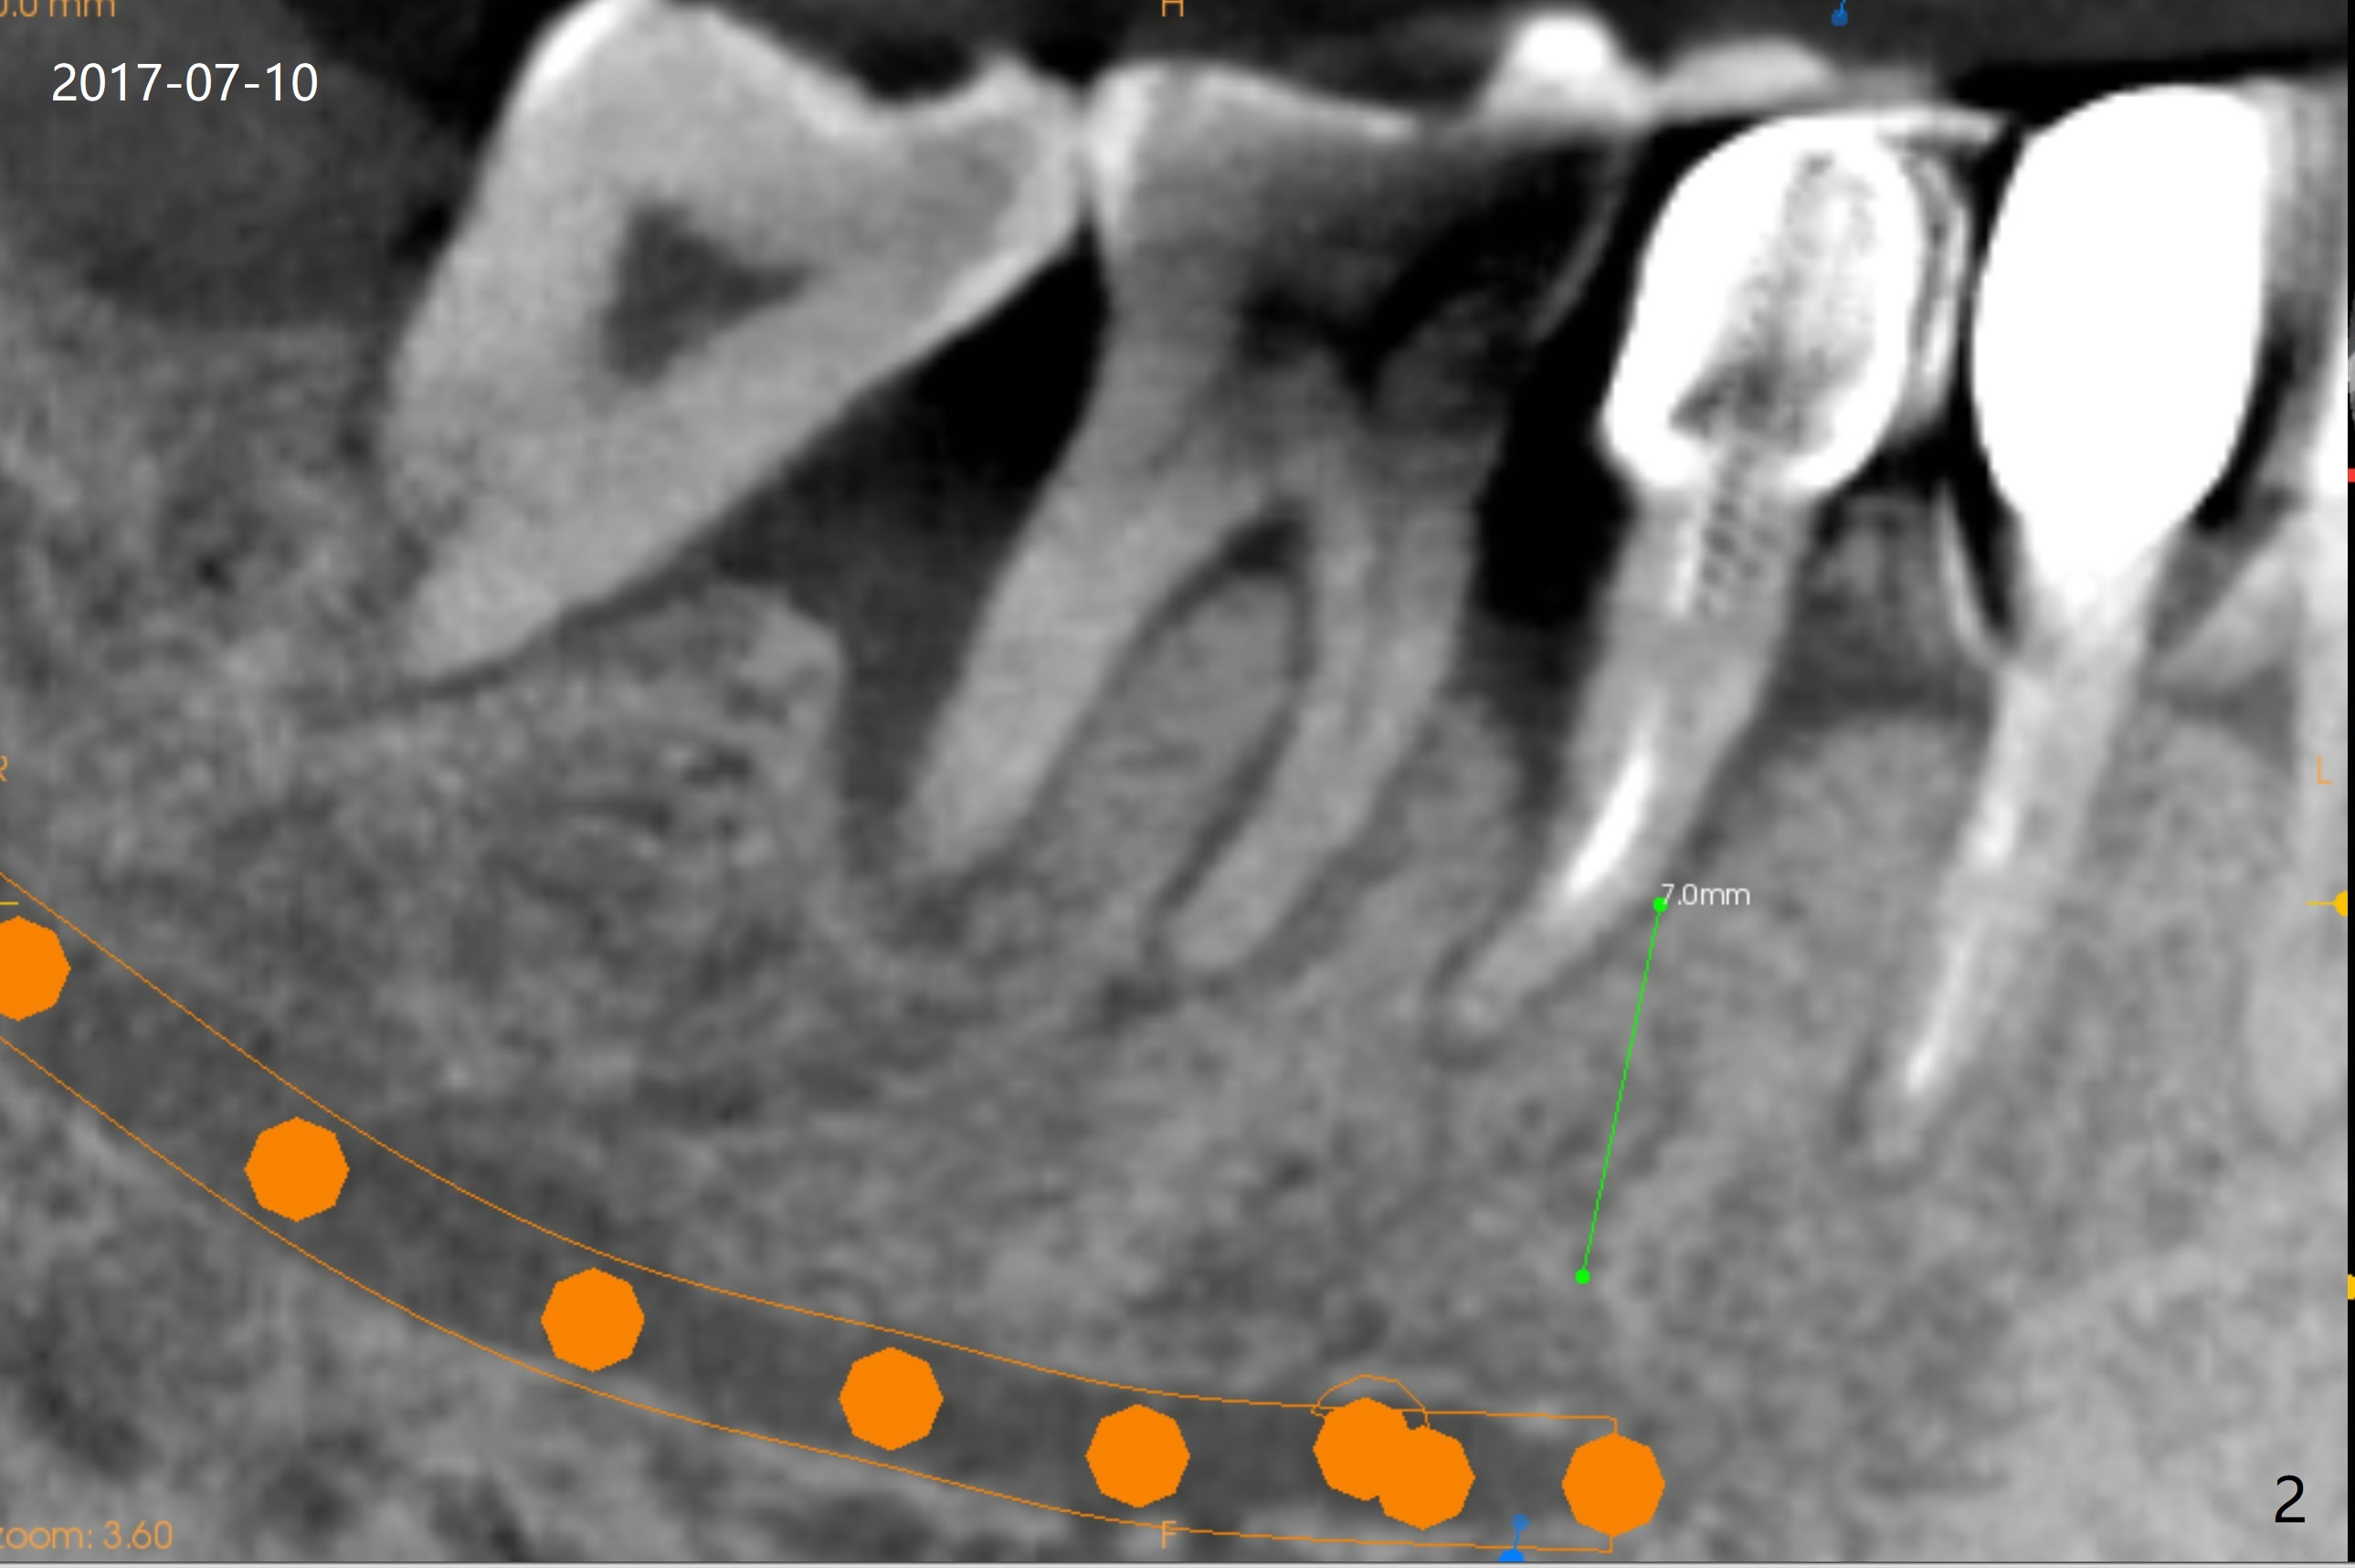

A 47-year-old man cannot chew in the lower right quadrant due to mobility of the tooth #29, which has a post (Fig.1 <). It appears that there is a buccal vertical fracture line. After extraction, osteotomy will be initiated in the mesiolingual aspect of the socket for 7 mm (Fig.2,3). The bone is dense (600-1,000 units); drills are required. Take a PA to confirm the trajectory. Following sequential osteotomy, place a 4x11mm dummy implant before placing a 4x9 or 11 mm definitive one, depending on bone resorption in the last 6 months (compare Fig.2,3 vs. 1).